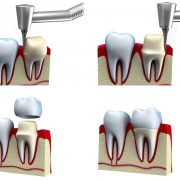

هنگامی که یک دندان پوسیدگی شدیدی داشته باشد و یا بخشی از آن در اثر شکستگی از بین برود، باید در هنگام درمان کمی حساسیت بیشتری برای آن صرف گردد. در چنین شرایطی معمولا باید ابتدا دندانپزشک درمان ریشه یا در اصطلاح عامیانه عصب کشی را انجام داده و سپس از یک لایه محافظ تحت عنوان روکش دندان استفاده کند. این کار باعث می شود تا بر عمر دندان درمان شده افزوده شود. اما گاهی ممکن است خود روکش دندان دردسر ساز گردد و لازم باشد تا فرد برای بهبود وضعیت آن مجددا به متخصص مراجعه نماید. درد دندان روکش شده یکی از معضلاتی است که بعد از انجام مراحل درمانی یک دندان خراب ممکن است شرایط را کمی پیچیده سازد.

به این ترتیب، شاید در ابتدا این گونه به نظر برسد که تنها درمان ریشه یک کار تخصصی است و نصب روکش را هر دندانپزشکی می تواند انجام دهد. در حالی که این گونه نبوده و نصب روکش نیز باید به صورت تخصصی و با مهارت صورت پذیرد تا کمترین عوارض را داشته باشد و احتمال بروز مشکلات بعدی نظیر درد دندان روکش شده را کاهش دهد. البته بهتر است این نکته را یادآور شویم که دندان روکش شده می تواند مدت کوتاهی بعد از نصب روکش و یا حتی ماه ها بعد دچار دردهای آزار دهنده گردد.

روکش دندان به کمک نوعی مواد بر روی دندان چسبانده می شود که خاصیت اسیدی دارد. در نتیجه ممکن است برای مدتی حساسیت دندان را بیشتر از حالت عادی تحریک کند و به هنگام خوردن غذا درد دندان روکش شده را در پی داشته باشد. بلند بودن روکش دندان بیشتر از حد طبیعی نیز می تواند عامل تشدید این درد باشد. به طور کلی، یکی از جمله مسائلی که باید به هنگام نصب روکش بر روی دندان توسط متخصص با دقت بررسی و رعایت شود، ارتفاع مناسب روکش دندان است. وقتی ارتفاع دندان روکش شده حتی به اندازه بسیار ناچیزی بلندتر از حد طبیعی دندان های فرد باشد منجر به وارد شدن فشار و در نتیجه درد دندان روکش شده می گردد.

جنس روکش دندان عصب کشی شده، باید از بهترین مواد باشد. اینکه دندانپزشک چقدر مهارت و تجربه داشته باشد، در انتخاب جنس مناسب برای روکش تاثیر گذار خواهد بود. روکش های دندانی که از جنس زیرکونیا و یا سرامیک هستند از جمله روکش هایی به شمار می آیند که از لحاظ زیبایی و دوام امتیازات فراوانی دارند.